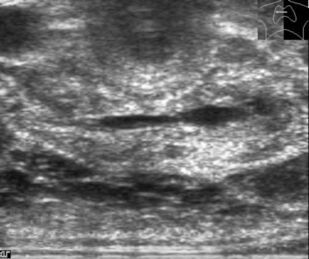

Ультразвуковое исследование оперированной щитовидной железы

В основу монографии положены материалы собственных исследований и практический опыт использования ультразвуковых методов диагностики при обследовании пациентов после хирургических вмешательств на щитовидной железе. Продемонстрированы диагностические возможности ультразвукового исследования в оценке состояния оперированной щитовидной железы в раннем и отдаленном послеоперационном периоде. Обобщена, систематизирована и представлена ультразвуковая семиотика зоны операции в ближайшие сроки после хирургических вмешательств и отражена динамика выявленных изменений. Убедительно показано, что ультразвуковое исследование может быть эффективным методом послеоперационного наблюдения.